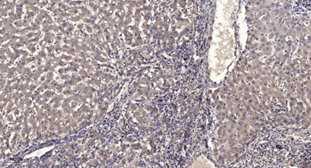

Immunohistochemical analysis of paraffin-embedded human liver cancer.

IHC-p 1:50-300